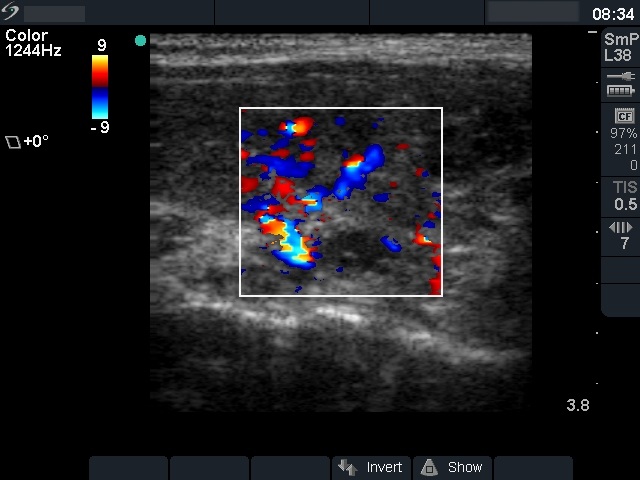

Ultrasonography: The echogenicity index of the thyroid was 50%. The vascularization was not significantly increased. There was a large hypoechogenic, inhomogeneous nodule in the upper part of the left lobe. Both the intranodular and the perinodular blood flows were increased.